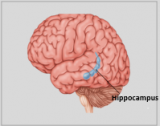

Neuroanatomie is de tak van de anatomie die de anatomie van het zenuwstelsel bestudeert, dat wil zeggen de structuur, functie en organisatie van het zenuwstelsel. Het zenuwstelsel is een van de meest complexe systemen in het menselijk lichaam en omvat de hersenen, het ruggenmerg, perifere zenuwen en zenuwganglia. Neuroanatomie houdt zich bezig met hoe deze structuren met elkaar verbonden zijn, hoe signalen tussen zenuwcellen worden doorgegeven en hoe de verschillende delen van het zenuwstelsel samenwerken om lichamelijke en cognitieve functies te besturen. Neuroanatomen maken gebruik van geavanceerde beeldvormingstechnieken, zoals MRI (magnetic resonance imaging), PET (positron emission tomography) en microscopie om de structuren en functies van het zenuwstelsel te visualiseren.